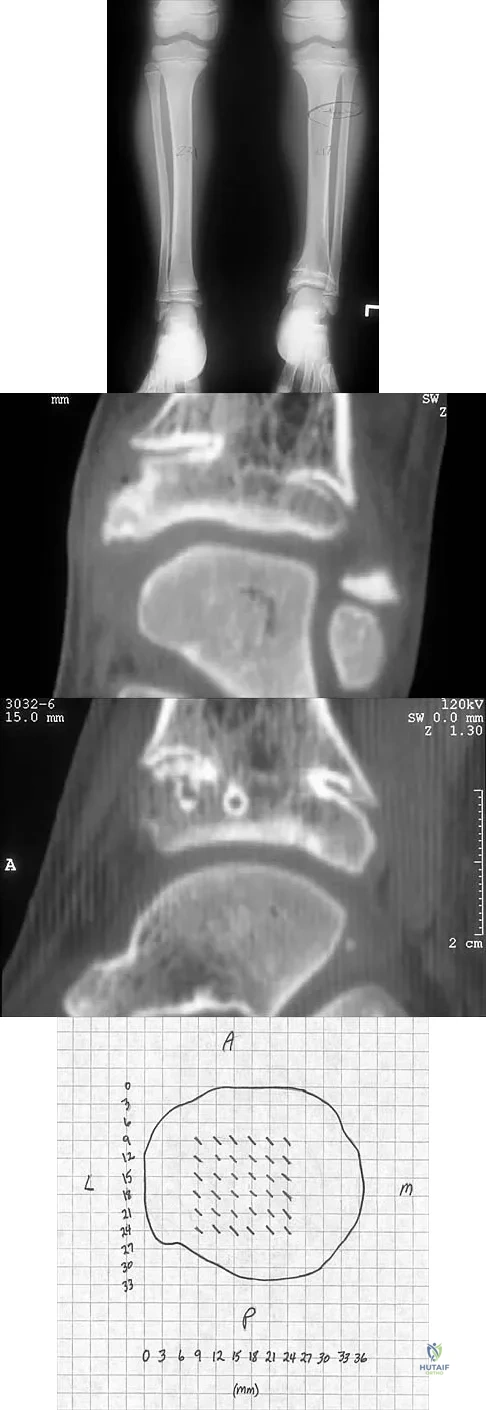

A 5-year-old girl sustained a comminuted Salter-Harris type IV fracture of the left distal tibia 2 years ago. The AP radiograph shown in Figure 54a reveals a growth arrest and a 1.4-cm limb-length discrepancy. The ankle is in approximately 20 degrees of varus. Figure 54b shows a coronal reconstruction image of the distal tibial physis, and Figure 54c shows a sagittal reconstruction image of the same area. On the sagittal reconstruction image, the bar extends from the 9-mm mark to the 24-mm mark in 3-mm increments. On the coronal image, the bar extends from the 9-mm mark to the 24-mm mark, also in 3-mm increments. A map of the physeal bar based on these measurements is shown in Figure 54d. Initial treatment should consist of

Explanation